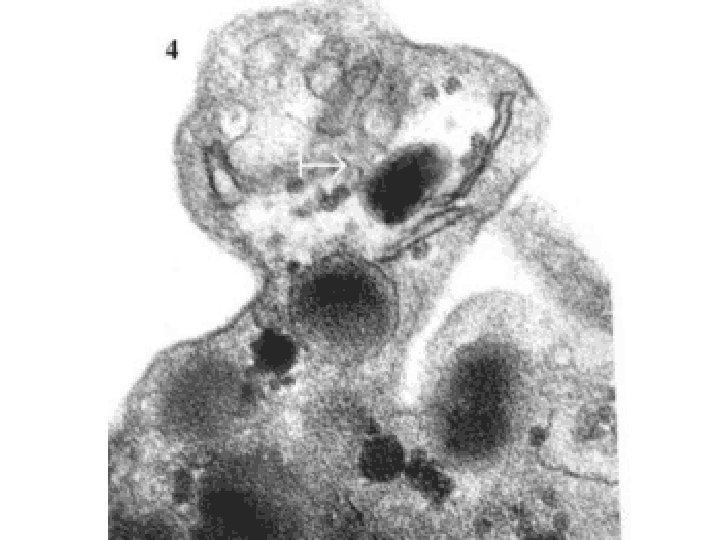

PLATELETS • ALPHA GRANULES – Fibrinogen – Fibronectin – Factor-V, Factor-VIII – Platelet factor 4, TGF-beta • DELTA GRANULES (DENSE BODIES) – ADP/ATP, Ca+, Histamine, Serotonin, Epineph. • With endothelium, form TISSUE FACTOR

NORMAL platelet on LEFT, “DEGRANULATING” ALPHA GRANULE ON RIGHT AT OPEN WHITE ARROW

PLATELET SECRETION • BOTH granules, α and δ • Binding of agonists to platelet surface receptors AND intracellular protein PHOSPHORYLATION